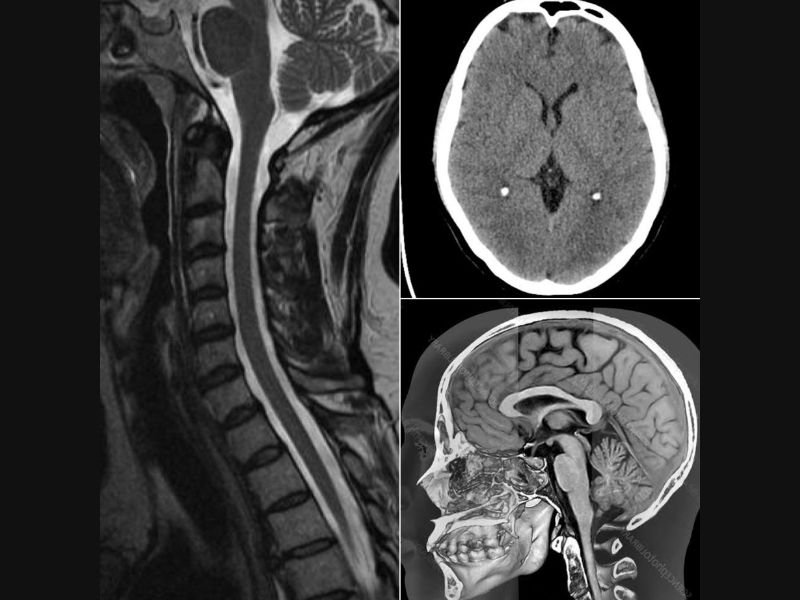

Led by Dr. Iqbal Singh (DM Neurology, MRCP(UK) SCE Neurology), our clinic offers advanced treatment for brain, spine, and nerve disorders.

We specialize in diagnosing complex neurological conditions including stroke, seizures, Parkinson’s disease, and more.

In our clinical practice, we offer specialized treatment for a wide range of neurological conditions including migraines, stroke, seizures, epilepsy, Parkinson’s disease, dementia, diabetic neuropathy, sciatica, multiple sclerosis, movement disorders, and more. Dr. Singh is dedicated to providing compassionate care and accurate diagnoses, helping patients regain their quality of life through personalized treatment plans and ongoing support.